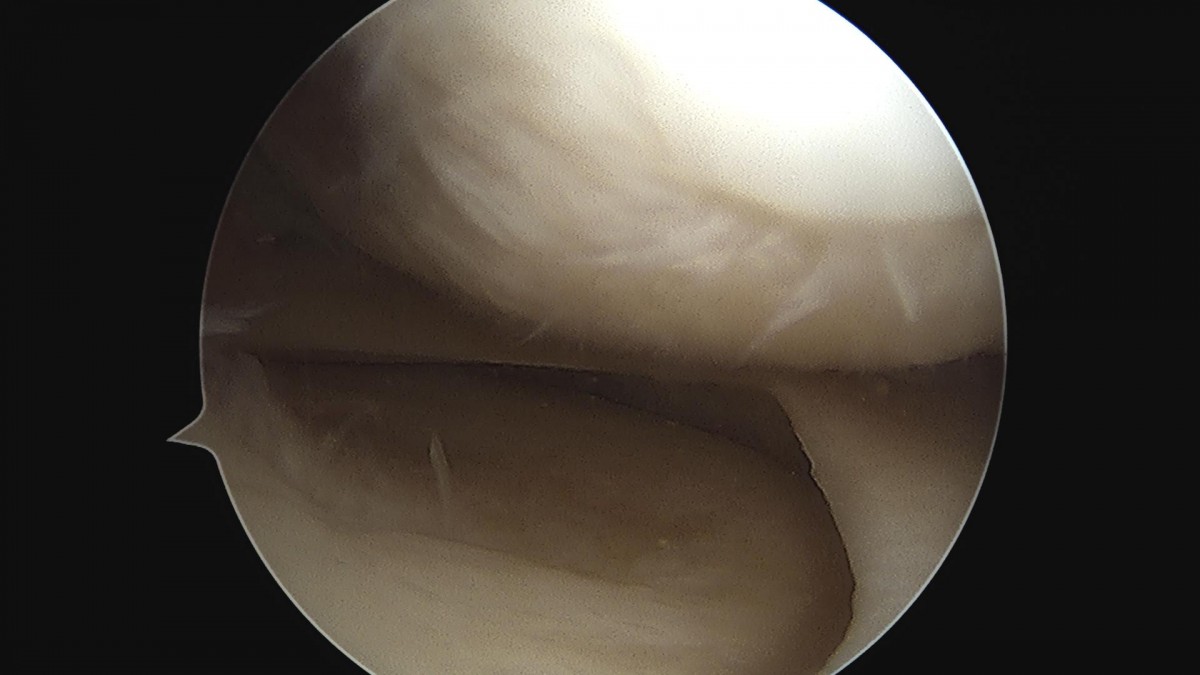

최원락 원장님 무릎 후방십자인대 재건술 김갑O 환자

작성자 최고관리자 댓글 0건 조회 893회 작성일 24-05-28 11:33